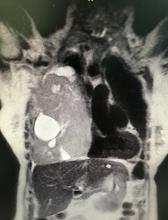

[4]Figure 2. Magnetic resonance, axial section, T2, where the tumor is observed, with cystic areas inside, which compresses without infiltrating adjacent tissues.

Puncion biopsy was performed with trucut. The Pathological Anatomy report is: fusocellular tumor, DC 34 negative, ASMA positive, S 100 negative, NSE negative, Ki 67 2% suggesting low grade leiomyosarcoma as a diagnosis. Magnetic resonance imaging was performed to visualize the presence of infiltration, mainly of large vessels, and studies for distant disease, without finding images compatible with metastasis (figures 2 and 3).